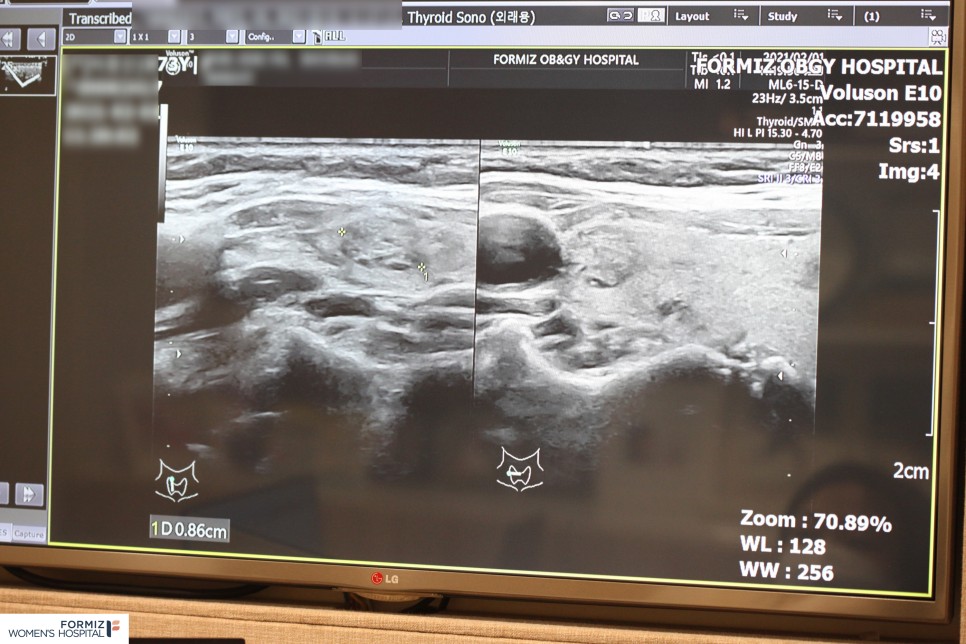

갑상선 결절(출처:포미즈여성병원)

제 목에 덩어리가 생겼을 때 우리 목에도 남녀를 불문하고 자주 덩어리가 발생합니다. 이를 #갑상선결절이라고 합니다. 특히 체내의 깊은 위치에 발생하는 것이 아니라 외부에서 충분히 눈으로 관찰할 수 있는 목 부위의 갑상선에서 병소가 나타나기 때문에 외관상의 이유로도 갑상선의 혹 제거가 필요할 수 있습니다. 목에 위치한 이 기관은 뇌하수체의 신호를 통해 호르몬을 분비하는 중요한 역할을 하기 때문에 크기가 커지면 갑상선 기능 문제를 일으킵니다.

결절에 따라 치료가 필요하다면 #갑상선 고주파 치료로도 가능하지만, 너무 크면 #갑상선절제술이 필요할 수 있습니다. 결절이 암일 경우는 50% 정도로 매우 낮고 증상도 거의 없지만 크기가 작아도 경계가 침대 형태를 하고 있고 딱딱한 고형이나 미세 석회화, 저친환경 소견이 있는 경우는 암의 가능성이 높아지므로 조직 검사와 함께 반드시 치료가 필요합니다. 치료방법으로 갑상선 절제술을 선택하기가 부담스러우면 갑상선 절제술 대신 고주파 전류를 활용한 RF에너지로 #갑상선 고주파 절제술을 선택할 수 있습니다.